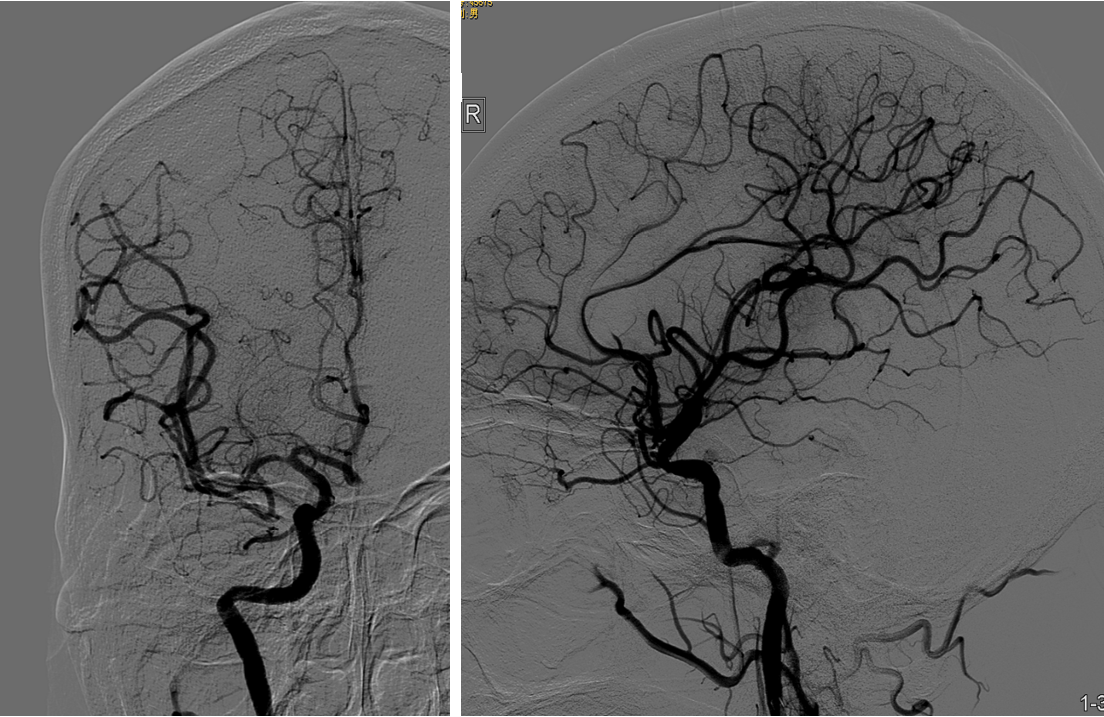

事件:M1中远段闭塞

策略:支架取栓

支架:蛟龙 4*30

技术:SWIM

该病例是心源性栓塞,血栓质韧,本例选用蛟龙4*30mm更长的取栓支架,更长长度提供更大表面积接触血栓,以独特的侧边螺旋开放结构,帮助快速高效一次三级再通。一篇研究回顾性分析了2011年6月到2017年3月使用直径4mm取栓支架及球囊指引导管作为首选治疗策略治疗ICA、MCA急性闭塞的病例。该研究中,4×30mm和 4×40mm被定义为长支架,4×20mm被定义为短支架。主要的临床结局是一次性取栓血管成功再通率(mTICI 2b/3)。研究共纳入420例患者,其中221例(53%)患者使用长支架,119例(47%)使用短支架。相对于短支架,长支架组一次性取栓血管开通率(62% vs 50%;P=0.01)和最终血管开通率(mTICI2b/3,98% vs 94%;P=0.01)更高。长支架一次性取栓成功开通率高的原因,可以从以下几方面来解释:长血栓会提供更大的表面积与取栓支架接触包裹血栓,也会在取栓过程中使张力均匀分布,在血管路径扭曲或者躁动的病人中,长支架通过增加可接受的误差范围来实现精确释放。更长的支架会增加取栓装置向血栓远端延伸的移动力,同时,在支架首个与血栓接触的网孔抓捕血栓失败的情况下,可以增加血栓取出的机会。[1]因此,通桥医疗即将上市的蛟龙4*30mm取栓支架在临床上的广泛应用值得期待。